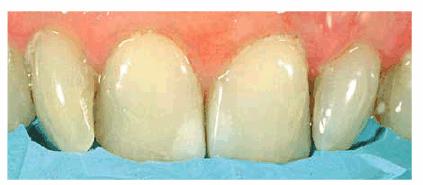

Figure 24-2A: This patient was dissatisfied with her crowded anterior teeth. Note how the gingival height differs between the central and lateral incisors.

Figure 24-2B: The dissimilar gingival heights did not bother the patient because her natural smile line concealed these irregularities.

Figure

24-2C: After a slight reproportioning of the six anterior teeth, direct

composite resin was placed and contoured (6-mm ET [Brasseler,

Figure 24-2D: The final result shows improved proportion in tooth size and form.